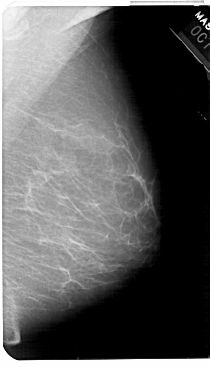

A_1441_1.RIGHT_MLO

RIGHT_MLO LINES 5491 PIXELS_PER_LINE 3136 BITS_PER_PIXEL 12 RESOLUTION 43.5 NON_OVERLAY